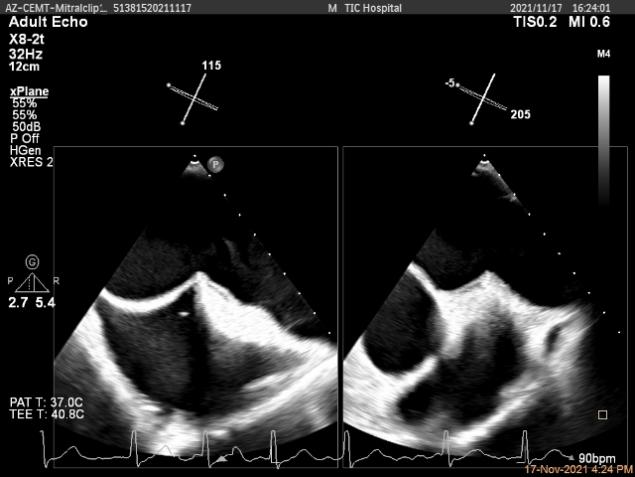

Multivue视图下将夹子正对AC区并调节Rotate

X-plane:下夹子尝试捕获靠近AC区脱垂瓣叶

将第二个夹子置于第一个夹子内侧尽量靠近,并调节Rotate呈尽量平行关系

成功抓捕内侧残余脱垂区域瓣叶